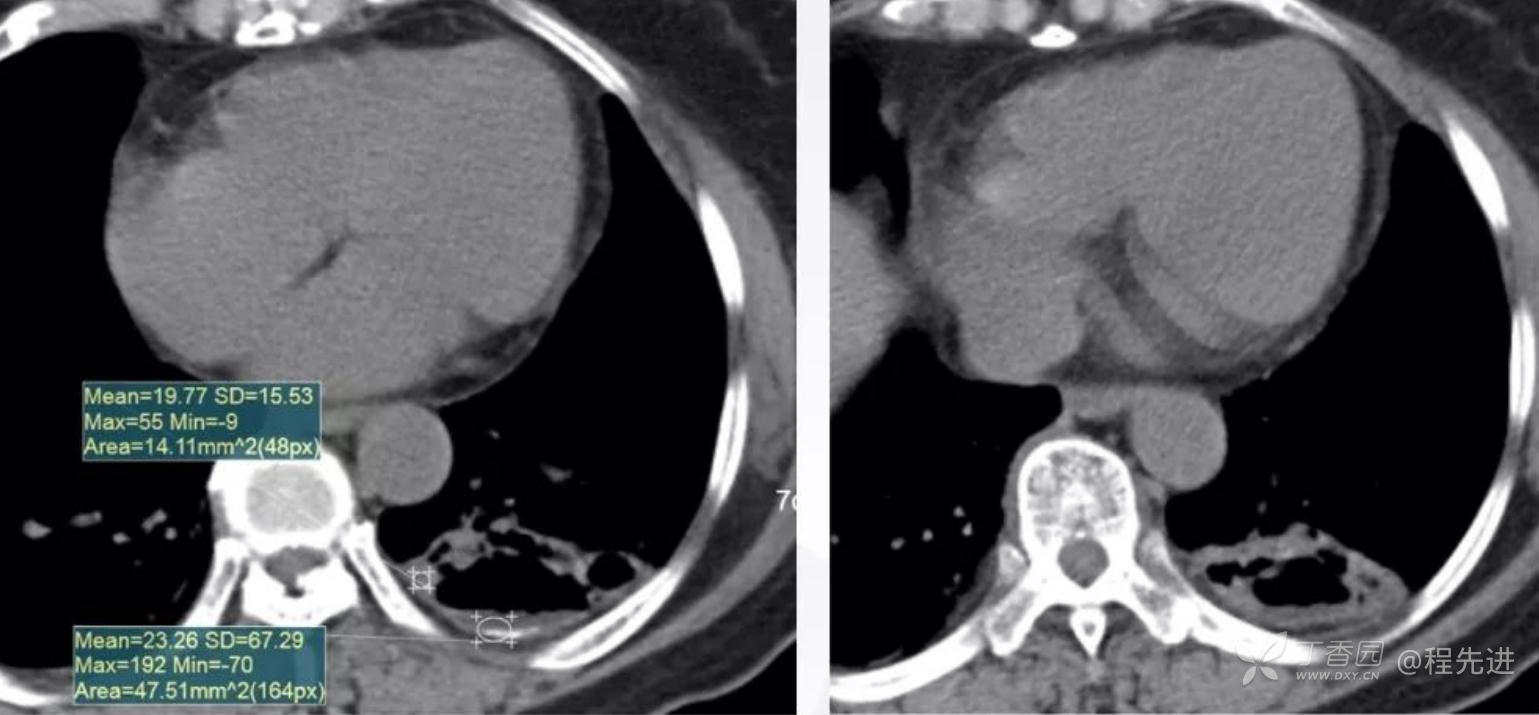

增强动脉期

静脉期